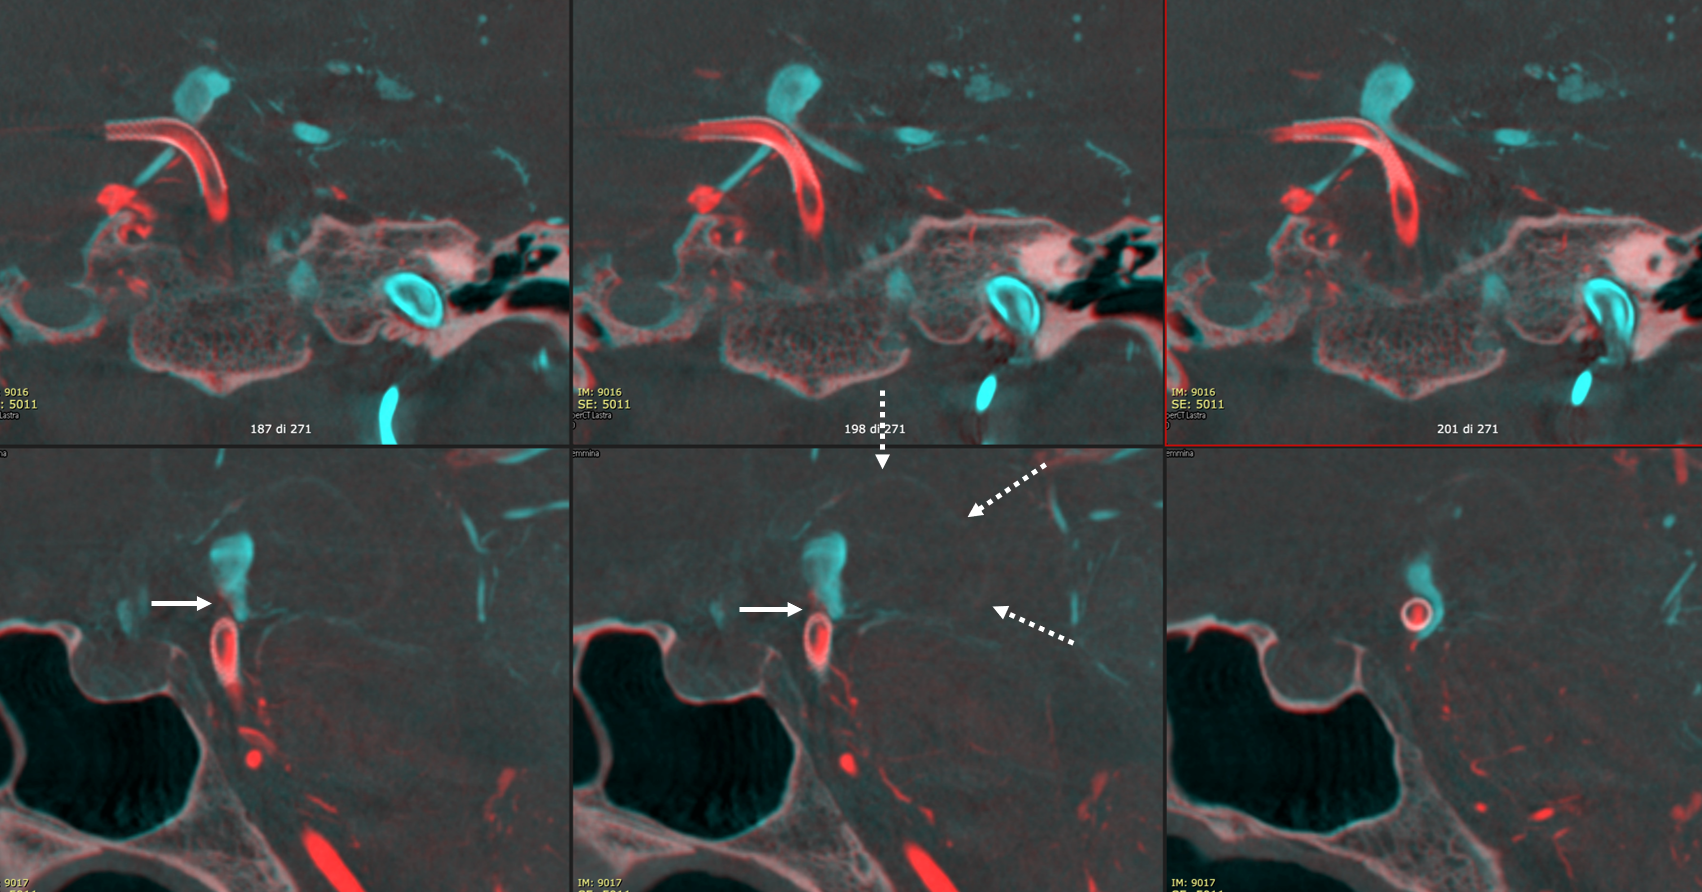

Vaso-CT, 22 cm FOV, 20 seconds acquisition, followed by a secondary reconstruction with 67% FOV and 5123 resolution; Pure contrast (300 mg/ml) manual injection in the left ICA. Thick MIP reconstructions

The protocol acquisition is the same of previous figure.

Fusion of the Vaso-CT of left ICA and posterior circulation (only one vertebral artery was injected, note the partial filling of the artery), thin sections; it helps in understanding the contribution of ICA and posterior circulation to the aneurysm (arrows) and the flow into the superior cerebellar arteries. The dashed arrows point to the wall of the thrombosed aneurysm.

To see how to make fusions, go to Philips AVM Fusions Embo and GK Targeting Page

Thick MIP reconstructions of the previous fusion